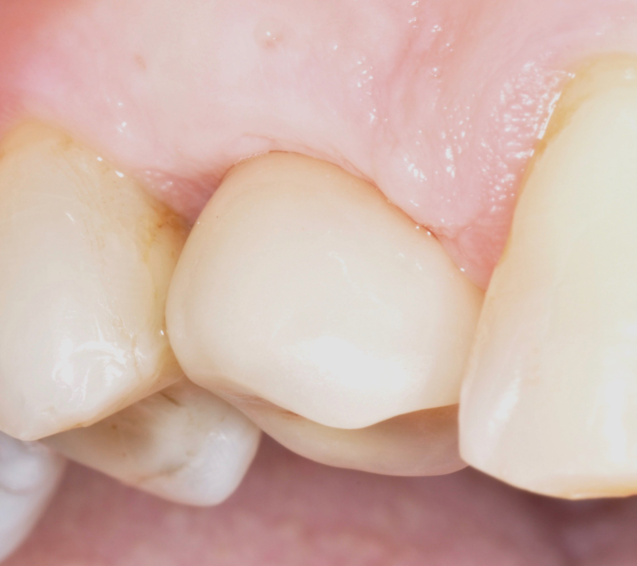

The parameters used to define peri-implant disease usually are: Probing Depth (PD), Crestal Bone Loss (CBL), Bleeding on Probing (BOP) and presence of suppuration and/or fistula.9 Peri-implant mucositis is characterised by soft tissues inflammation witnessed by BOP with or without PD deepening but no effects on the crestal bone while peri-implantitis is characterised by CBL, BOP alone or in conjunction with pus, with or without PD deepening. (Figs. 1, 2 and 3) display the diagnostic steps of a case of peri-implantitis. While mucositis allows a complete healing, peri-implantitis is not reversible.12

Fig.1: Case 1. Peri-implant probing reveals a PPD of 9mm and pus.